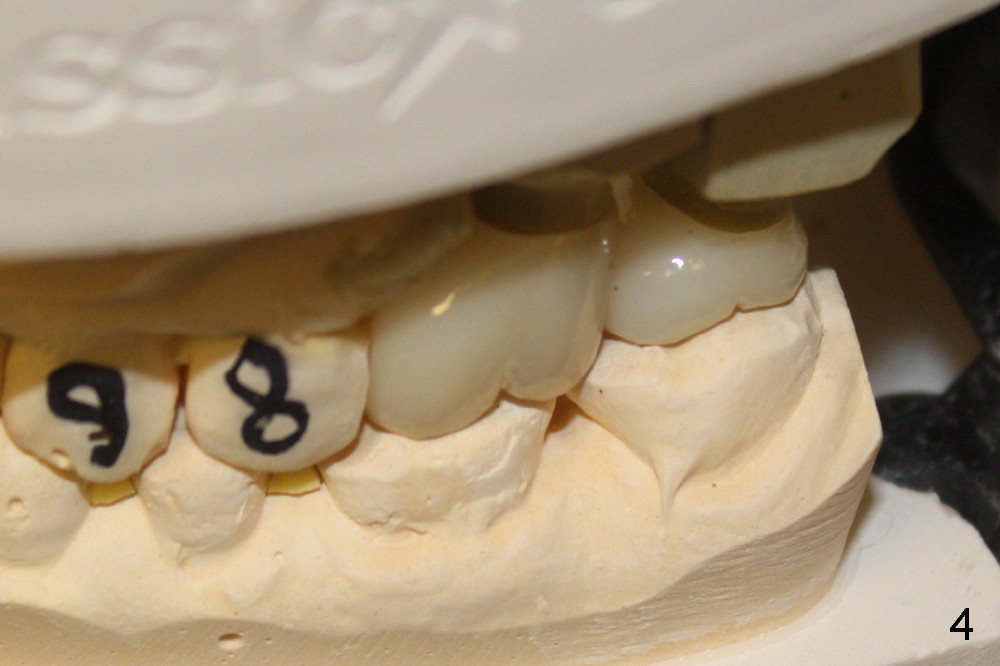

On the day of delivery, the model is studied (Fig.1 (buccal), 2 (lingual), 3 (occlusal)). The implant at the site of the1st molar (#1 in Fig.1-3) is placed distally; it is at the distobuccal cusp (DB in Fig.1). The crown of the 2nd molar (#2) has to extend mesially (Fig.2 arrow) for compensation. The buccolingual width of these two upper molar crowns is reduced, as evidenced by the edge to edge or mild cross bite of occlusal scheme (Fig.4). Anyway, it appears that the implant at the first molar is malpositioned. How to prevent it?